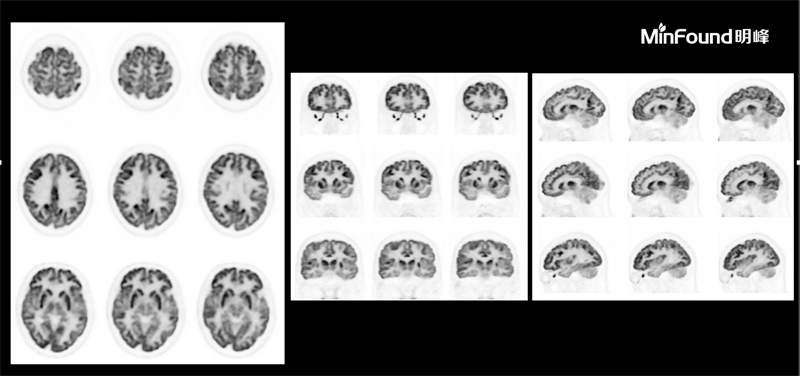

ScintCare PET/CT 730T

ScintCare PET/CT 730T employs a 4th-generation PET detector where lutetium-yttrium oxyorthosilicate (LYSO) crystals are individually coupled to SiPM detectors without the optical conductor (1: 1 coupling and 100% coverage). The digital SiPM detector considerably minimizes photon loss, resulting in improved time resolution (380 ps), system sensitivity (23.5 cps / kBq), and image uniformity, ultimately resulting in high-resolution images under well-curated radiation dose control.

臨床畫廊